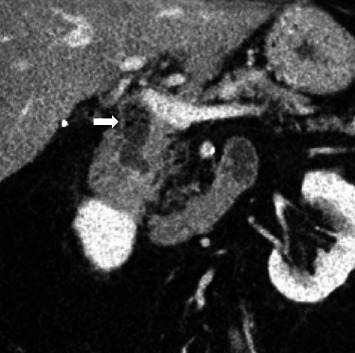

Computed tomography (CT) scan showed a 1.6 cm air and fluid-filled collection initially interpreted as a duodenal diverticulum. Upon review, this was felt to represent the intrapancreatic portion of the distal CBD (Figure 1).